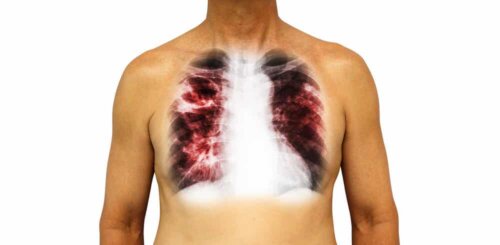

2. De vanligaste smittsamma sjukdomarna: Tuberkulos

Detta är en annan av de vanligaste smittsamma sjukdomarna på global nivå. Specifikt är det en av de tio främsta dödsorsakerna i världen, som drabbade 10 miljoner människor 2018. Av dessa 10 miljoner dog 1,5 miljoner människor, enligt uppgifter från Världshälsoorganisationen (WHO).

De bakterier som orsakar denna sjukdom – Mycobacterium tuberculosis – har blivit mycket resistenta mot konventionell behandling, och detta har orsakat en folkhälsokris och ett hot mot hälsosäkerheten. Trots detta lyckas vi ändå varje år uppnå en cirka 2 % minskning av smittfrekvensen.

Tuberkulos överförs genom luften och den infekterade personen kan antingen utveckla symtom eller inte. Av alla smittade personer uppvisar endast 10 % symtom. Bland de vanligaste symtomen kan vi hitta följande: